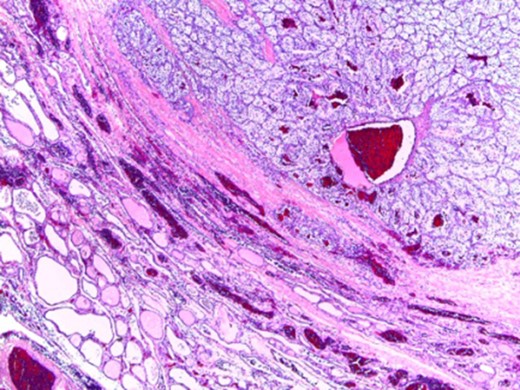

In microscopic evaluation the tumor had a predominantly ‘clear cell’ morphology, typical of RCC as shown in Figs 2 and 3.

Normal thyroid tissue on the lower left corner; clear cells in the upper right quadrant.

The histologic diagnosis was aided by the use of immunohistochemistry which was positive for PAX8 (Fig. 4) and CD10, and negative for thyroid transcription factor 1 (TTF-1) (Fig. 5), vimentin and chromogranin.